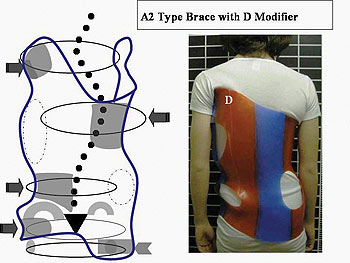

كيف يعمل حزام اعوجاج العمود الفقري؟

الحزام يعمل بطريقة ذكية تعتمد على:

- توجيه نمو العمود الفقري

- تقليل الضغط على المناطق المنحنية

- دعم الوضعية الصحيحة للجسم

هل كل الأطفال يحتاجون نفس نوع الحزام؟

لا، يتم تصميم الحزام حسب حالة كل طفل.

التطور الكبير في تصميم الأحزمة الطبية جعل علاج اعوجاج العمود الفقري عند المراهقين أكثر نجاحًا وأقل إزعاجًا. باستخدام تقنيات التصوير الثلاثي الأبعاد والمحاكاة الرقمية، أصبح الحزام أكثر خفة وراحة، ويعطي نتائج أفضل في تصحيح الانحناء والتواء العمود الفقري.